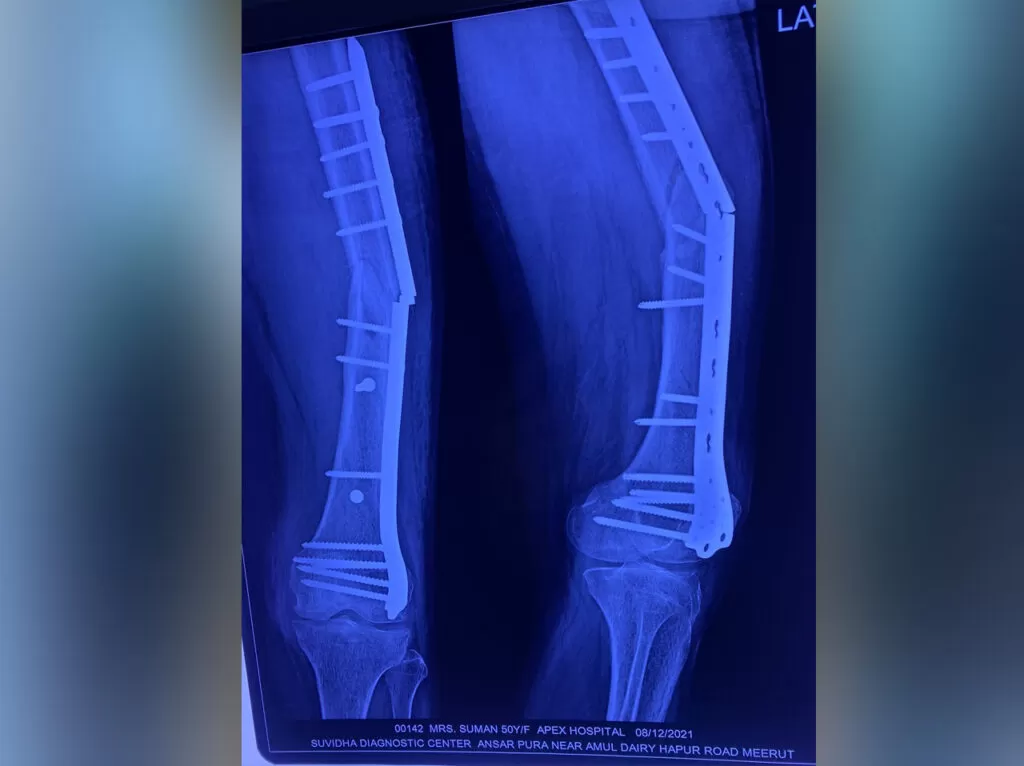

Mrs. Suman

Name: Mrs. Suman

Date of Operation: 8 Dec 2021

Age: 57 Years